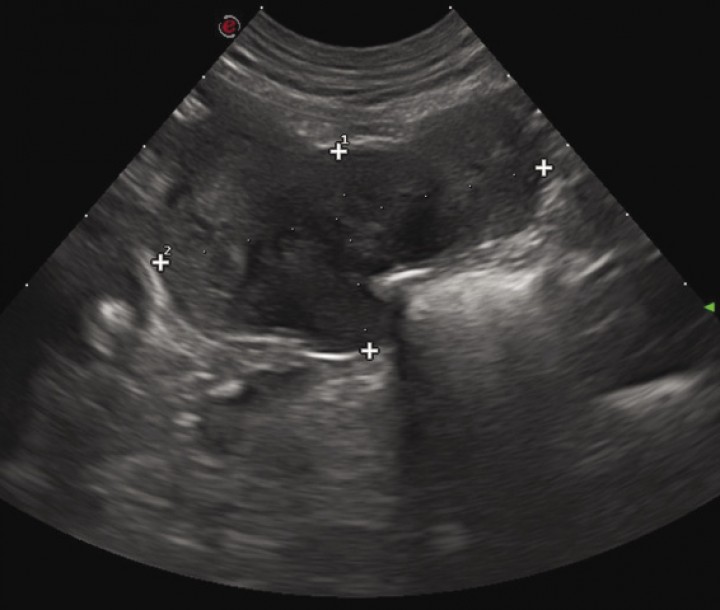

Six dogs with a histological confirmed diagnosis of GIST and c-kit positive results were enrolled in the study. One dog previously diagnosed of leiomyoma was diagnosed with GIST at the beginning of the study after immunohistochemical assessment. There were 4 females and 2 males of the following breeds: Bobtail, American Pitbull, American Staffordshire Terrier, Spanish Water Dog, Labrador, and Yorkshire Terrier. Mean age at presentation was 10.8 years ranging from 6.5 to 12.1 years. Clinical signs at presentation were nonspecific in 3 dogs including anorexia (3), lethargy (3), vomiting (3), abdominal pain and enlargement (3), diarrhea (1), weight loss (1) and fever (1). Three dogs had no any clinical sign related to the GIST (Table 1). Blood tests did not show any relevant abnormalities. In all 6 dogs ultrasonography revealed the presence of abdominal masses (Fig. 1) suggesting a diagnosis of neoplastic disease. A clear link between abdominal mass and specific abdominal structure was undetermined in 3 out of 6 cases, although in one dog the mass was thought to be in contact with intestinal loops (Table 2). Thoracic radiographs performed in 4 out of 6 dogs did not show any evidence of metastasis. All dogs underwent laparotomy and two dogs were previously diagnosed with abdominal perforation, which was confirmed at surgery. One of these two dogs was euthanatized during surgery because of the presence of gross metastasis in the liver and omentum. These findings were missed on the abdominal ultrasound and were subsequently confirmed at necropsy. One of the GIST was located on jejunum, and the other 5 on cecum (Fig. 2). In all 5 dogs, complete macroscopic resection was achieved. Peri-operative complications were not seen in any case except for one dog that developed acute pancreatitis, but he had a good outcome being discharged 6 days later. Immunohistochemical assessment yielded generalized positive results for c-kit in all samples, thus confirming the diagnosis of GIST (Fig. 3). Only one out of 6 tumors was incomplete resected based on light microscope. Specific histological details are summarized in Table 3. Adjunctive therapy with TKI after surgery was recommended in 3 cases and was declined in one case. One dog underwent treatment course of imatinib mesylate (Glivec®, Novartis Pharma AG, Basilea) at a dose of 12 mg/kg/PO/SID for 6 months and not adverse effects related to treatment were seen. The remaining dog received a combination of firocoxib (Previcox®, Merial Laboratorios, S.A., San Cugat del Vallés) and toceranib (Palladia®, Zoetis, Parsippany, New Jersey) at a dose of 2.5 mg/kg/PO three times per week for 1 year. The treatment was discontinued due to side effects including vomiting and diarrhea. One dog had a relapse 36 days after surgery. Blood test at that moment revealed hypoglycemia and abdominal ultrasound findings suggested metastatic process located on mesenteric lymph nodes although it was not histologically confirmed. Initially hypoglycemia was controlled with a continuous 5% dextrose infusion and treatment with TIK was proposed as long-term therapy, but owners declined further treatment. Mean survival time for the 6 dogs (including the one euthanized at surgery) was 17.5 months. Mean survival time for the 5 dogs was 20.6 months (range from 1 to 43 months). Two of them were still alive by the time of writing this paper and did not show any evidence of relapse.

<p>Ultrasound appearance of one of the GIST located on cecum.</p>

Ultrasound appearance of one of the GIST located on cecum.

In our study abdominal ultrasound was 100% sensitive for diagnosis of abdominal tumor disease, but failed to both determine the anatomical origin of the tumor in three cases and to detect liver and omental metastasis in one case. Nevertheless, in dogs abdominal ultrasound has been reported as very accurate test to identified the actual tumor origin and to predict metastasis.[ Hanazono K, Fukumoto S, Hirayama K, et al: Predicting metastatic potential of gastrointestinal stromal tumors in dog by ultrasonography. J Vet Med Sci 2012; 74:1477-82. [PubMed] , Hobbs J, Sutherland-Smith J, Penninck D, et al: Ultrasonographic features of canine gastrointestinal stromal tumors compared to other gastroinetestinal spindle cell tumors. Vet Radiol Ultrasound 2015 56(4):432-8. [PubMed] ] In human medicine, ultrasonography is the first line diagnostic test in cases of GIST but in some cases, such as large abdominal masses without clear anatomic, computed tomography (CT) is the best option.[ Corless CL: Gastrointestinal stromal tumors: what do we know now?. Modern Pathology 2014; 27:1-16.  [PubMed] , Peixoto A, Costa-Moreira P, Silva M, et al: Gastrointestinal stromal tumors in the imatinib era: 15 years’ experience of a tertiary center. J Gastrointest Oncol 2018 9(2):358-362. [PubMed] ] Therefore, in dogs with large abdominal masses CT should be considered prior to surgery. One study in dogs revealed that the presence of an irregular margin pattern in ultrasound could be a marker for malignant behavior,[ Hanazono K, Fukumoto S, Hirayama K, et al: Predicting metastatic potential of gastrointestinal stromal tumors in dog by ultrasonography. J Vet Med Sci 2012; 74:1477-82. [PubMed] ] similar to humans.[ Ohashi S, Okamura S, Urano F, et al: Clinical malignancy risk of assessed by endoscopic ultrasonography. Dig Endosc 2006 18:256-262. ] The same authors suggested that internal echogenicity could be a prognostic marker for metastasis as tumors with large internal hypoechogenic areas (indicative of necrosis areas) were categorized as high-risk. Moreover, these tumors tended to be larger in size than types categorized as intermediate or low-risk.[ Hanazono K, Fukumoto S, Hirayama K, et al: Predicting metastatic potential of gastrointestinal stromal tumors in dog by ultrasonography. J Vet Med Sci 2012; 74:1477-82. [PubMed] ] These results agreed with earlier studies reporting that areas of necrosis positively correlated with tumor size[ Gillespie, V., Baer, K., Farrelly, J., Craft, D. and Luong, R: Canine gastrointestinal stromal tumors: Immunohistochemical Expression of CD34 and examination of prognostic indicators including proliferation makers Ki67 and AgNOR. Vet Pathol 2011: 48: 283-291. [PubMed] ] and larger tumor diameter could be a negative prognostic indicator in dogs.[ Maas CPHJ, Haar GT, Van Der, Gaag I, Kirpensteijin, J: Reclassification of small intestinal and cecal smooth muscle tumors in 72 dogs: clinical, histological, and immunohistochemical evaluation. Vet Surg 2007; 36:302-313. [PubMed] ] However, these studies had some limitations, so these conclusions should be assumed with caution. Similar to other studies[ Maas CPHJ, Haar GT, Van Der, Gaag I, Kirpensteijin, J: Reclassification of small intestinal and cecal smooth muscle tumors in 72 dogs: clinical, histological, and immunohistochemical evaluation. Vet Surg 2007; 36:302-313. [PubMed] , Russell K, Mehler S, Skorupski K, et al: Clinical and immunohistochemical differentiation of gastrointestinal stromal tumors from leiomyosarcomas in dogs: 42 cases (1990–2003). J Am VetMed Assoc 2007; 230(9):1329-1333. [PubMed] , Hobbs J, Sutherland-Smith J, Penninck D, et al: Ultrasonographic features of canine gastrointestinal stromal tumors compared to other gastroinetestinal spindle cell tumors. Vet Radiol Ultrasound 2015 56(4):432-8. [PubMed] ] thoracic metastasis were not seen in our patients.